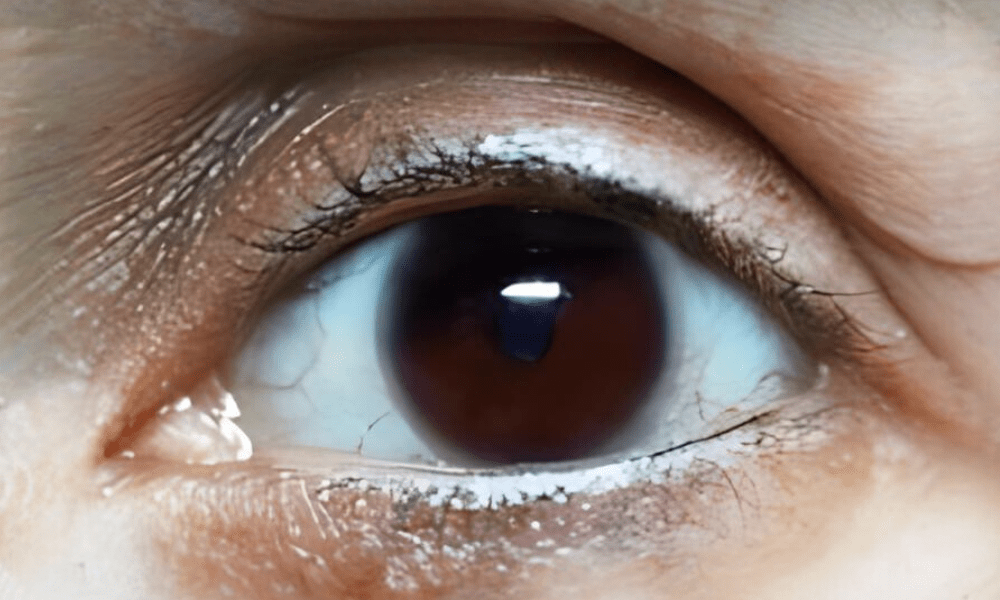

Mature Cataract Lens

Brown Cataract Lens

Normal Lens